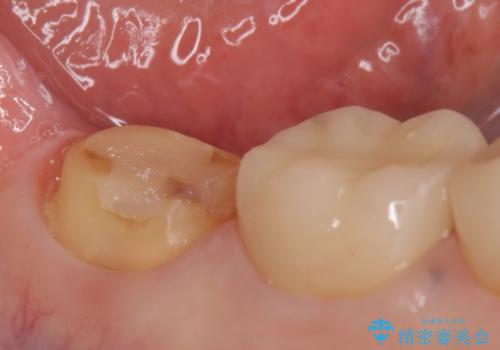

- 右下の奥歯でものを咬むと違和感があるので診て欲しいといらっしゃった方の症例です。

右下6は神経が死んでいたため根管治療を行い、オールセラミッククラウンによる補綴を行いました。

右下7は冷たいものがしみていたため、銀歯を除去後、オールセラミッククラウンによる補綴を行いました。